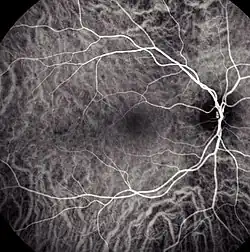

Choroidal blood flow revealed with indocyanine green angiography

Indocyanine green angiography (ICGA) is a diagnostic procedure used to examine choroidal blood flow and associated pathology. Indocyanine green (ICG) is a water soluble cyanine dye which shows fluorescence in near-infrared (790–805 nm) range, with peak spectral absorption of 800-810 nm in blood.[1][2] The near infrared light used in ICGA penetrates ocular pigments such as melanin and xanthophyll, as well as exudates and thin layers of sub-retinal vessels.[3] Age-related macular degeneration is the third main cause of blindness worldwide, and it is the leading cause of blindness in industrialized countries.[4] Indocyanine green angiography is widely used to study choroidal neovascularization in patients with exudative age-related macular degeneration.[5] In nonexudative AMD, ICGA is used in classification of drusen and associated subretinal deposits.[5]